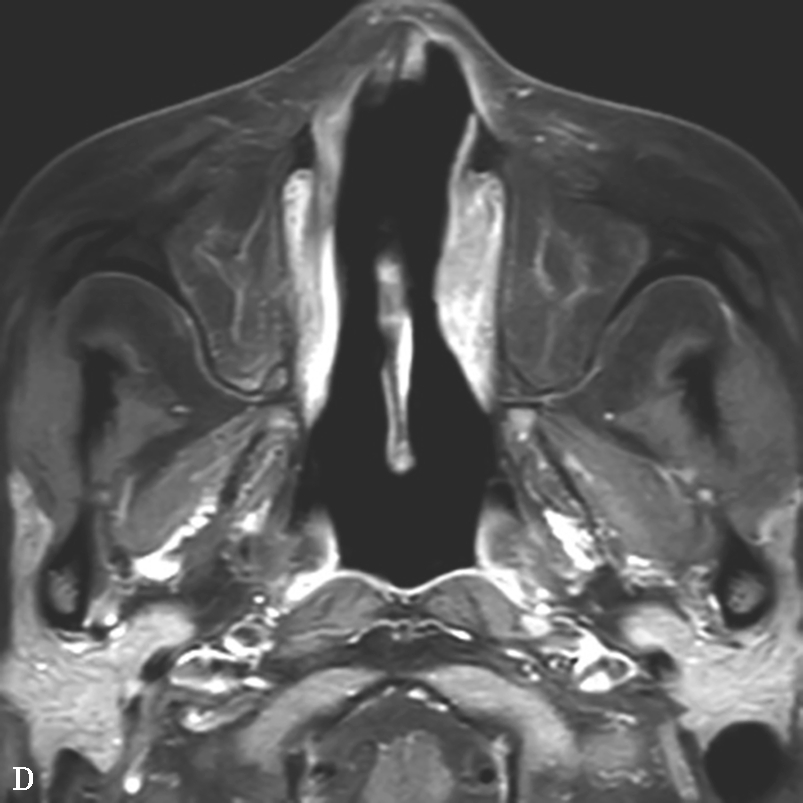

图1-3-25 慢性侵袭性真菌性鼻窦炎

A、B.横断面CT及冠状面CT骨窗,示右侧蝶窦可见软组织影充填,蝶窦侧壁欠光整,骨皮质略模糊;C.横断面T 2 WI,示右侧蝶窦病变呈混杂等略低信号,右侧海绵窦受累增厚;D.横断面T 1 WI,示病变呈略高信号;E.横断面T 1 WI+FS+C,示蝶窦腔病变大部分无强化,可见不规则索条状明显强化影,窦腔边缘黏膜增厚强化,右侧海绵窦受累增厚强化,斜坡及Meckel腔脑膜增厚强化;F.冠状面T 1 WI+FS+C,示蝶窦病变破坏鞍底骨质,累及鞍上及右侧海绵窦,垂体受累轻到中度不均匀强化,蝶窦黏膜弥漫性增厚强化